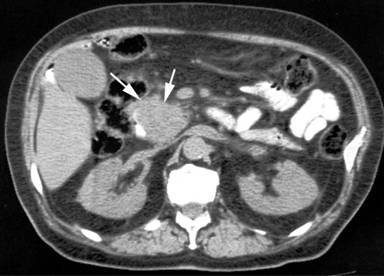

Abdominal ultrasonography showed a distended gallbladder, dilatation of the intra- and extra-hepatic bile ducts but not gallstones. An endoscopic retrograde cholangiopancreatography (ERCP) revealed a bulging papilla with infiltrative growth at the ampulla of Vater but endoscopic biopsies were inconclusive. The performed computed tomography (CT) of the abdomen showed enlargement of the pancreatic head (Figure 1). There were no hepatic lesions or enlarged intra-abdominal lymph nodes. These findings were confirmed at operation, and a classical Whipple’s pancreaticoduodenectomy was performed.

|

Figure 1. Abdominal CT scan showing enlargement of the pancreatic head (arrows). |